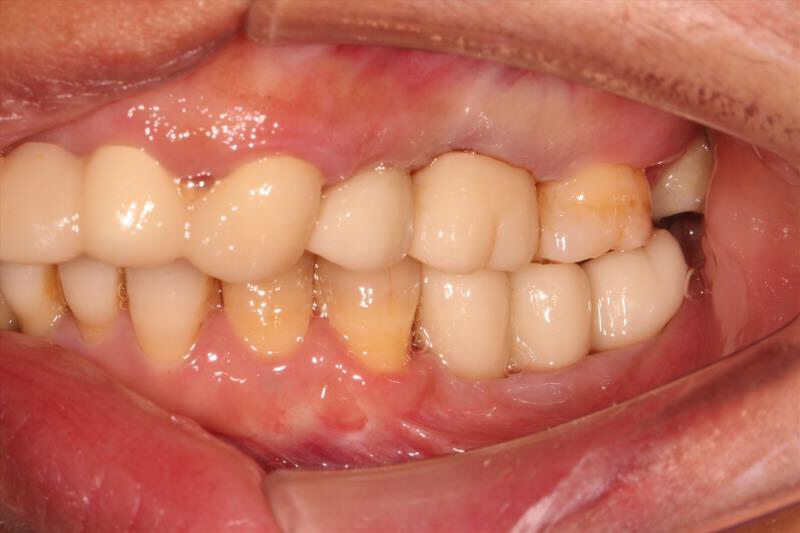

患者中年女性,左下5、6、7缺失多年,牙槽骨吸收较多,CBCT可见牙槽骨高度不足,距离下颌神经管比较近,所以为这位患者选择了短植体进行种植,术中植骨盖膜,历时7个月戴上了牙齿,患者使用满意。